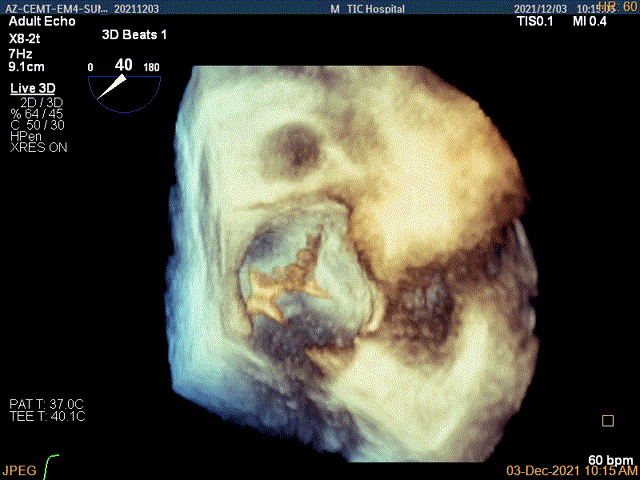

3D视图下到达目标位置

3D视图下开夹子旋转使得clip的两个arm与MV对合线垂直

X-plane:下夹子尝试先捕获1区脱垂瓣叶